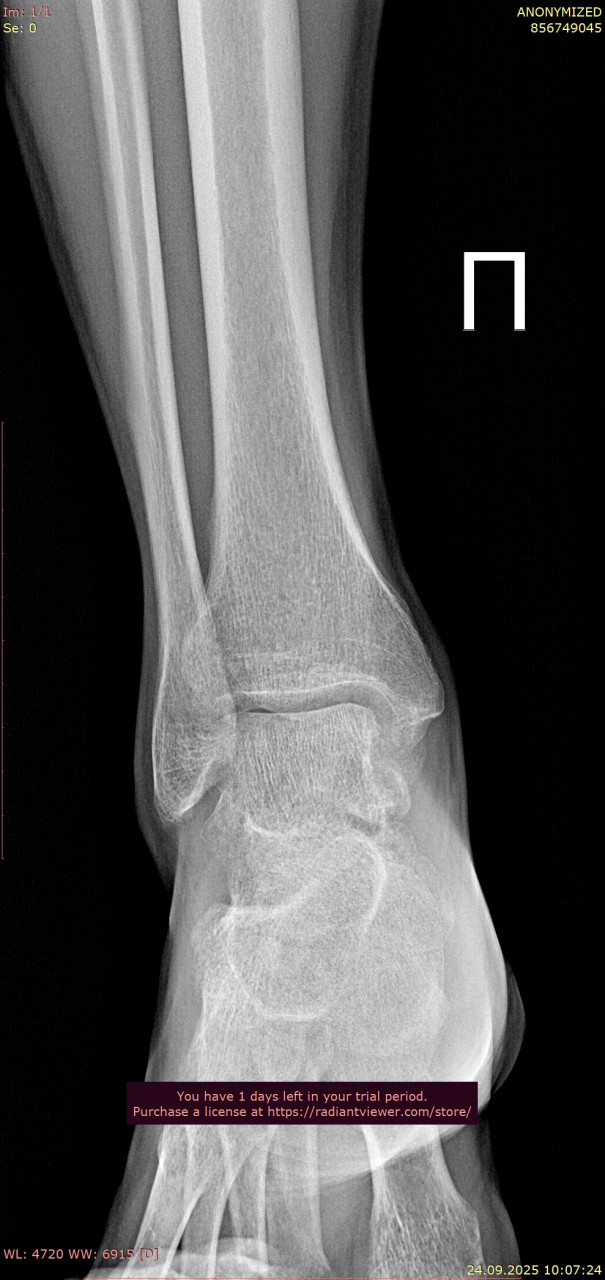

Посмотрите, пожалуйста, снимки голеностопного сустава от 23.06.2025, когда был перелом, и спустя 3 месяца от 24.09.2025. Как Вы считаете, полностью ли восстановился голеностопный сустав, артроз обязательно приведет к болям при ходьбе в ближайшие годы, можно ли этого избежать? Ведь до пенсии теперь еще далеко( Сейчас собираюсь подбирать ортопедические стельки, может посоветуете как это сделать подешевле, из за длительной нетрудоспособности денег почти нет. Смог прикрепить только одну проекцию от дыты переломаб еще есть снимки стопы, там перелом плюсневых.

Здравствуйте. На контрольных снимках костная структура выглядит восстановленной, консолидация произошла, признаков грубых осложнений нет. Артроз после таких травм возможен, но при отсутствии боли и отёка риск выраженных проблем в ближайшие годы невелик, особенно если продолжать ЛФК и постепенно наращивать нагрузку. Стельки лучше подбирать индивидуально, даже самые простые готовые варианты из аптек или ортопедических салонов могут помочь и стоят дешевле индивидуальных.